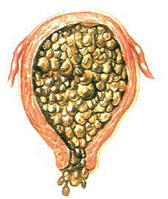

为绒毛基质微血管消失,从而绒毛基质积液,形成大小不等泡,形似葡萄,故称为 葡萄胎 (hydatidiform mole)。有完全性怀部分性之分,大多数为完全性葡萄胎。临床诊断葡萄胎皆系指完全性葡萄胎而言;部分葡萄胎伴有胎盘组织或/及胎儿者,则冠以部分性葡萄胎。在自然流产的组织中发现40%病人有一定的水泡样变性,但不诊断为葡萄胎。

①完全性葡萄胎:胎盘绒毛全部受累,无胎儿及其附属物,宫腔内充满水泡;②部分性葡萄胎:仅部分胎盘绒毛发生水泡状变性,宫腔内尚有存活或已死的胚胎。

1.完全性葡萄胎:是一种有滋养细胞增生的发生异常的胎盘。并且一般不会出现胎儿或者胚胎。

完全性葡萄胎的囊泡比较圆,外层多数围这滋养细胞的增生。